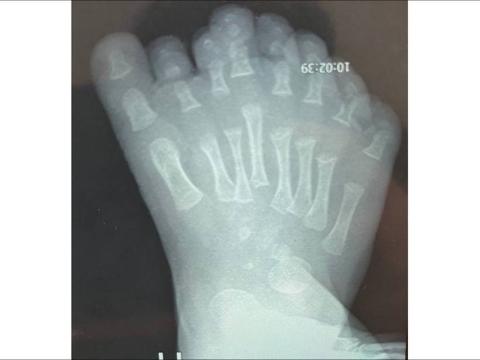

Специалисты отделения травматологии и ортопедии Ивано-Матренинской детской клинической больницы провели операцию ребёнку с полидактилией. У мальчика был врождённый дефект, из-за которого на ноге сформировалось восемь пальцев. Об этом сообщается в социальных сетях медицинского учреждения.

— Особенность этой полидактилии заключается в том, что увеличено не только количество фаланг пальцев, но и количество плюсневых костей, что приводит к нарушению конфигурации стопы в целом. Мы решили удалить лишние фаланги и плюсневые кости второго, третьего и четвёртого пальцев. Это решение обусловлено особенностями кровоснабжения стопы, а также позволит сохранить полноценную опору на стопу и привести её к нормальным размерам без излишней травматизации тканей, — сказал травматолог-ортопед отделения травматологии и ортопедии ОГАУЗ ГИМДКБ Илья Зеленин.